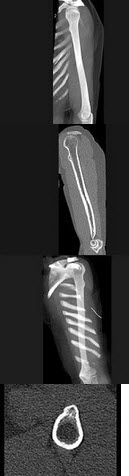

59、单项选择题

女,12岁,左前臂外翻畸形4年,摄片如图所示,最可能的诊断是()

A.奥利氏病

B.马德隆氏畸形

C.先天性干骺端发育不全

D.软骨发育不全

E.以上均不正确